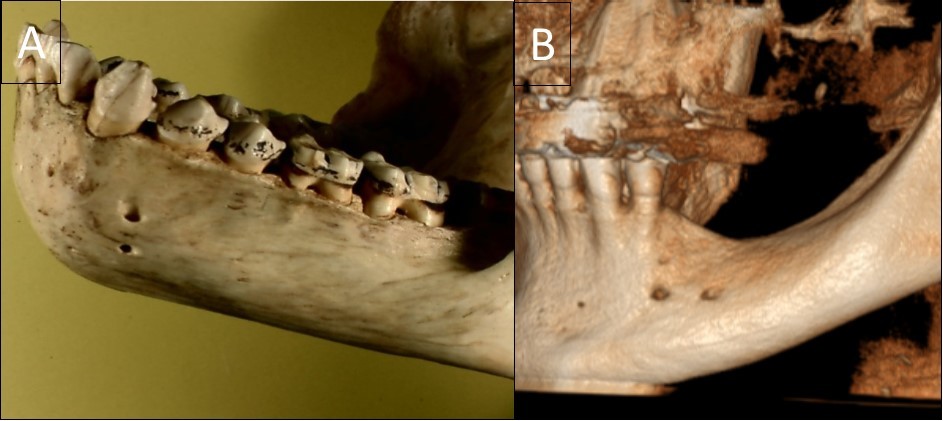

Figure 2.A general view of a gorilla mandible with a vertical double foramen (A) and a human mandible with a horizontal double foramen (B).

A general view of a gorilla mandible with a vertical double foramen (A) and a human mandible with a horizontal double foramen (B).